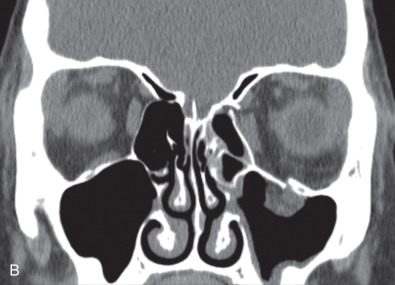

While comminuted “blow-out” fractures are commonly seen in adults, linear, minimally displaced fractures occur more commonly in the pediatric orbit. The elasticity of the pediatric orbital bone is the key difference, resulting in a unique clinical presentation: trapdoor fractures. The trapdoor pattern describes the entrapment of orbital tissue, the most concerning of which are extraocular muscles, in a linear orbital wall fracture that is usually minimally or non-displaced ( Fig. 2.3.4 ). When force is placed on the orbit, the intraorbital pressure increases and creates a fracture of the orbital wall. Periorbital tissue is then pushed into the open fracture. In the adult, the fracture remains open and displaced, resulting in the classic “blow-out” presentation characterized by enophthalmos and/or hypoglobus. In the pediatric patient, however, the bone fracture is incomplete, and the partially fractured bone will rapidly recoil back to the original position trapping the periorbital tissue and leading to possible strangulation. Furthermore, children presenting with radiographic “blow out” fractures often times do not present with globe malposition as do their adult counterparts ( Fig. 2.3.5 ). The periosteum and supporting soft tissue may remain intact, maintaining orbital volume despite a large displaced wall fracture.